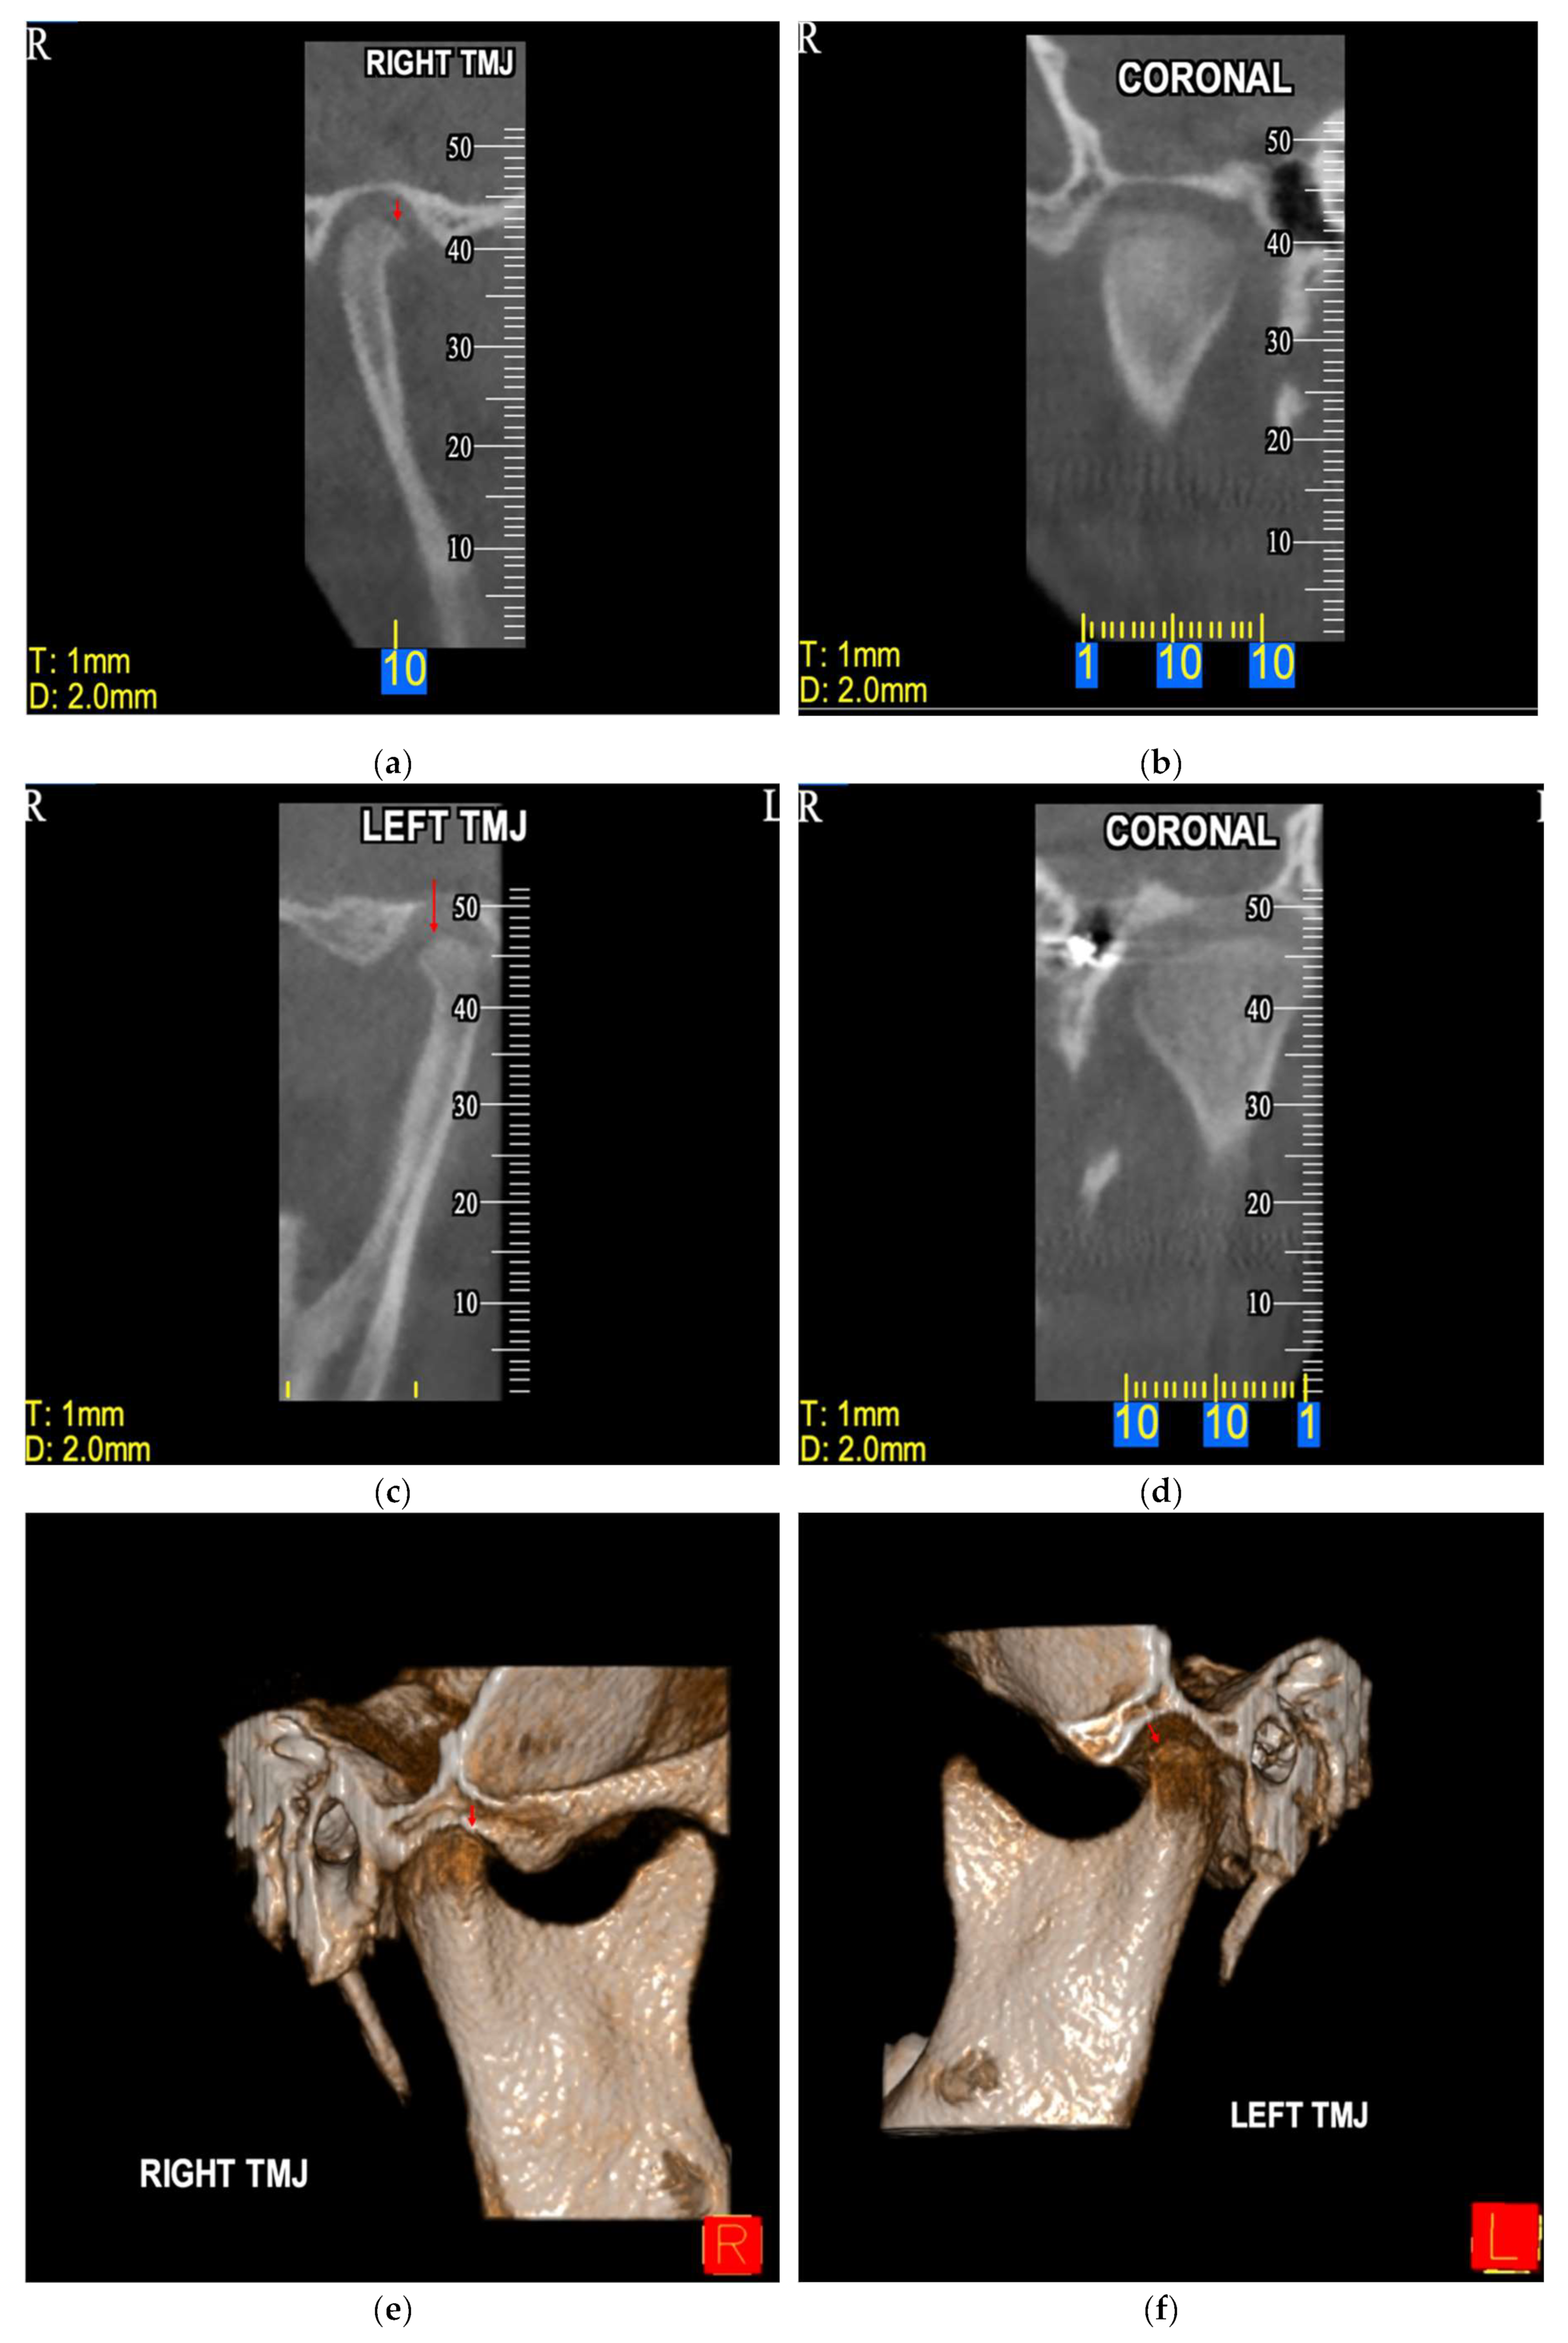

74.17% of the total sample presented IFs (Table 2). More specifically, the prevalence of IFs was 97.5% in the case group and 62.5% in the control group (Table 2). According to the Chi-square test, the higher prevalence of IFs that was reported in the case group compared with the control group was statistically significant [χ2 = 17.05, degrees of freedom (df) = 1, p <0.001, Table 3]. Representative radiographic images of CL/P patients are depicted in Figure 1, Figure 2 and Figure 3.

Figure 1. Orthopantomogram (OPT) of a male patient (10.9 years old) diagnosed with CLP—UL presenting various incidental findings: agenesis of tooth 12 (bold red arrow), malposition of tooth 22 (thin diagonal red arrow), impaction of tooth 23 (thin diagonal red arrow), rotation of tooth 11 (thin vertical red arrows), supernumerary tooth between teeth 22-23 (red circle) and deviated nasal septum to the right (red asterisk).